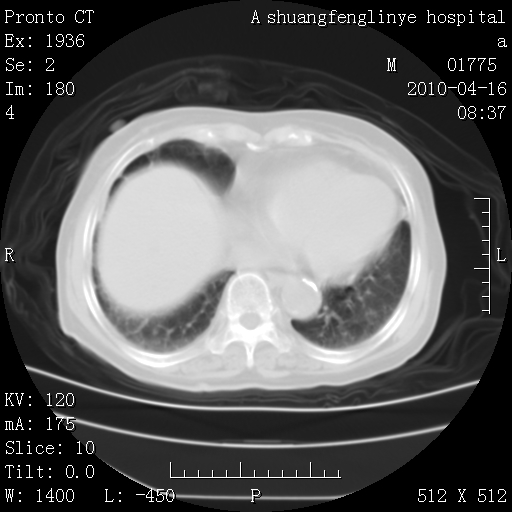

标题: CT25784:咳痰、请会诊!结核? [打印本页]

标题: CT25784:咳痰、请会诊!结核?

老年肺间质纤维化,肺动脉高压-----肺心病。

慢支肺气肿,左上陈旧性结核,主动脉冠脉钙化

典型 夹层动脉瘤。 内膜瓣钙化移位

1)左肺上叶结核(纤维、增殖病灶)。2)冠状动脉及主动脉钙化。

1)左肺上叶结核(纤维、增殖病灶)。2)冠状动脉及主动脉钙化。肺动脉高压